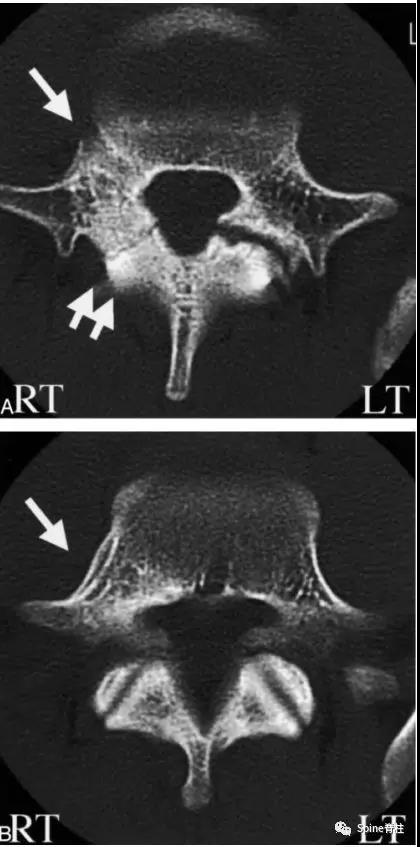

图:起始CT提示L5左侧峡部裂(双箭头),起始CT检查后2个月复查可见出现右侧椎弓根裂(单箭头),4个月复查可见椎弓根裂愈合(单箭头)